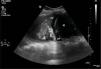

We hereby present two cases of lung ultrasound in two patients admitted to the ICU with respiratory failure due to ARDS who remained on mechanical ventilation for more than seven days. Fig. 1 shows the “fluid bronchogram” sign (arrows) consisting of ramified linear images that correspond to distended bronchi filled with fluid and lack of air over hypoechogenic pulmonary parenchyma and simulate blood vessels but distinguish from them by having a wall (hyperechogenic) and lack of Doppler signal. It suggests pulmonary atelectasis due to central airway obstruction (CAO). Fig. 2 shows pulmonary parenchyma with hyperechogenic dots representative of air inside the bronchus. It is the “air bronchogram” sign. In the appropriate clinical context, it is indicative of infectious lung condensation (mobile bronchogram) or compression atelectasis (static bronchogram).